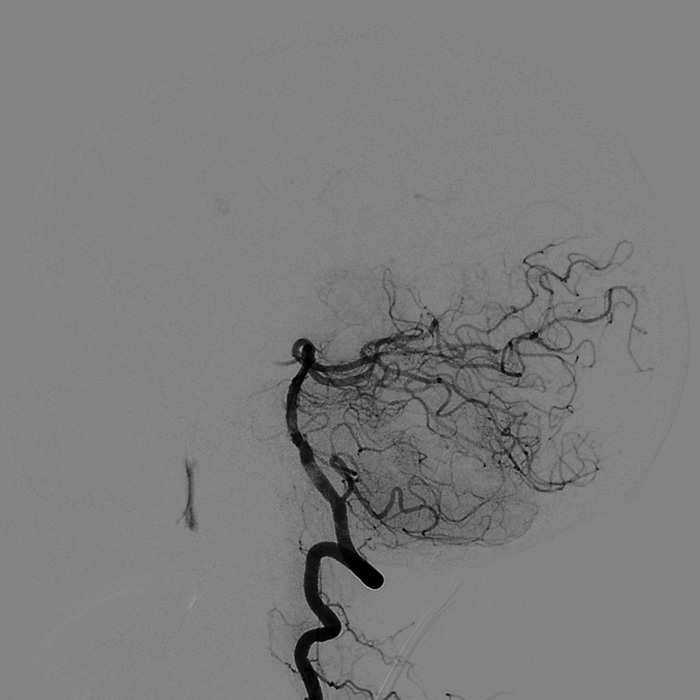

??? 9月3日00:10 ?神經(jīng)外科團(tuán)隊(duì)?wèi){借深厚的介入功底及對(duì)顱腦血管病變治療的經(jīng)驗(yàn),沉穩(wěn)地將栓子取出,血管恢復(fù)再通,梗塞區(qū)血流灌注隨即恢復(fù)。

取栓后造影顯示雙側(cè)小腦上動(dòng)脈及雙側(cè)大腦后動(dòng)脈充盈良好